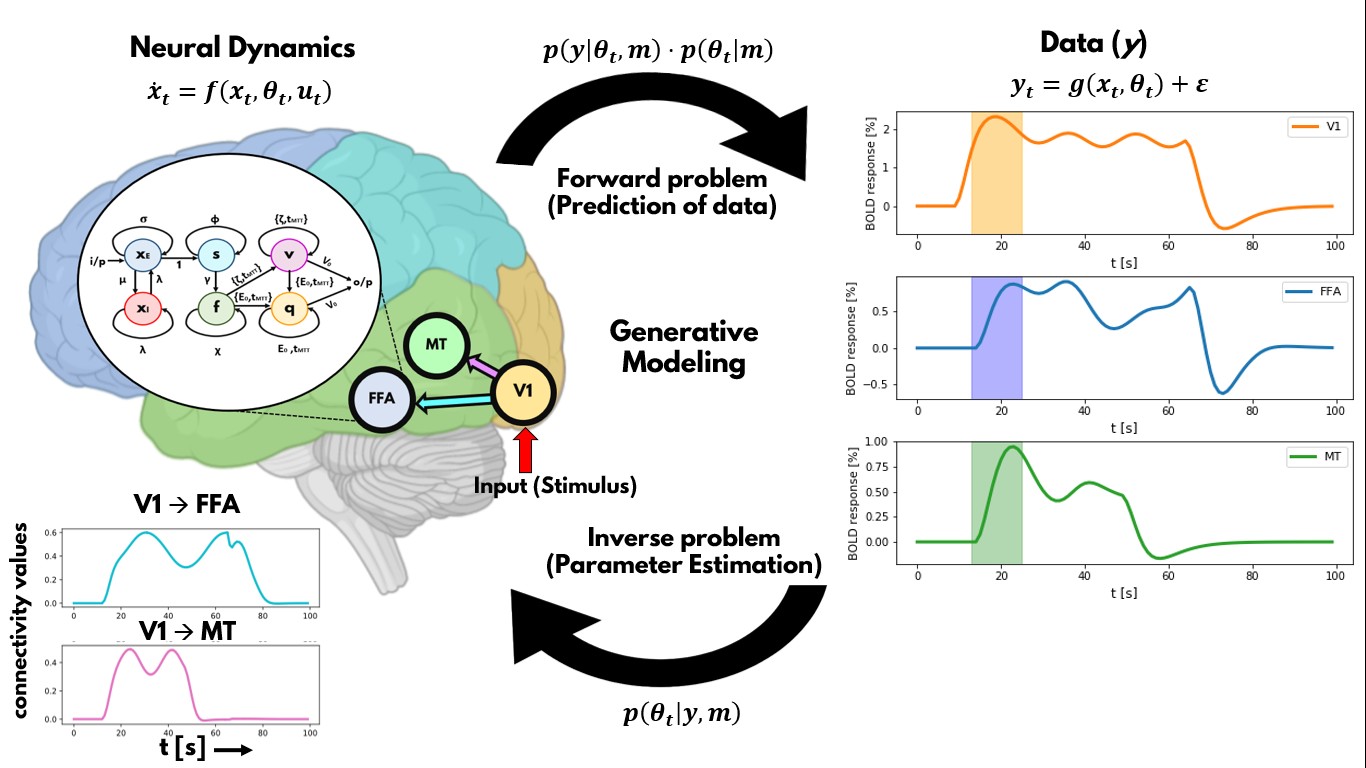

The overall goal of this research line is to develop artificial neuronal network approaches that reproduces brain MR imaging data, representing the next neuroscience revolution (“neurobiologically-plausible artificial intelligence (AI) models”), fundamentally advancing our understanding of human brain function. We cannot develop more advanced models of brain functioning without a more thorough understanding of brain dynamics and networks. However, our understanding of the human brain is limited by biased approaches and limitations of traditional statistics, thus forcing us to rely on artificial machine learning algorithms to provide an alternative perspective. The goal is to dynamically and comprehensively describe cognitive processes as an emergent property of brain networks on healthy subjects and patients. This will then allow characterizing human brain function on a single-subject level for the purpose of personalized medicine. In the individual projects of this research line, we develop and apply advanced AI methods on human fMRI data and develop dynamic generative models of brain connectivity (aka Dynamic Causal Modeling).